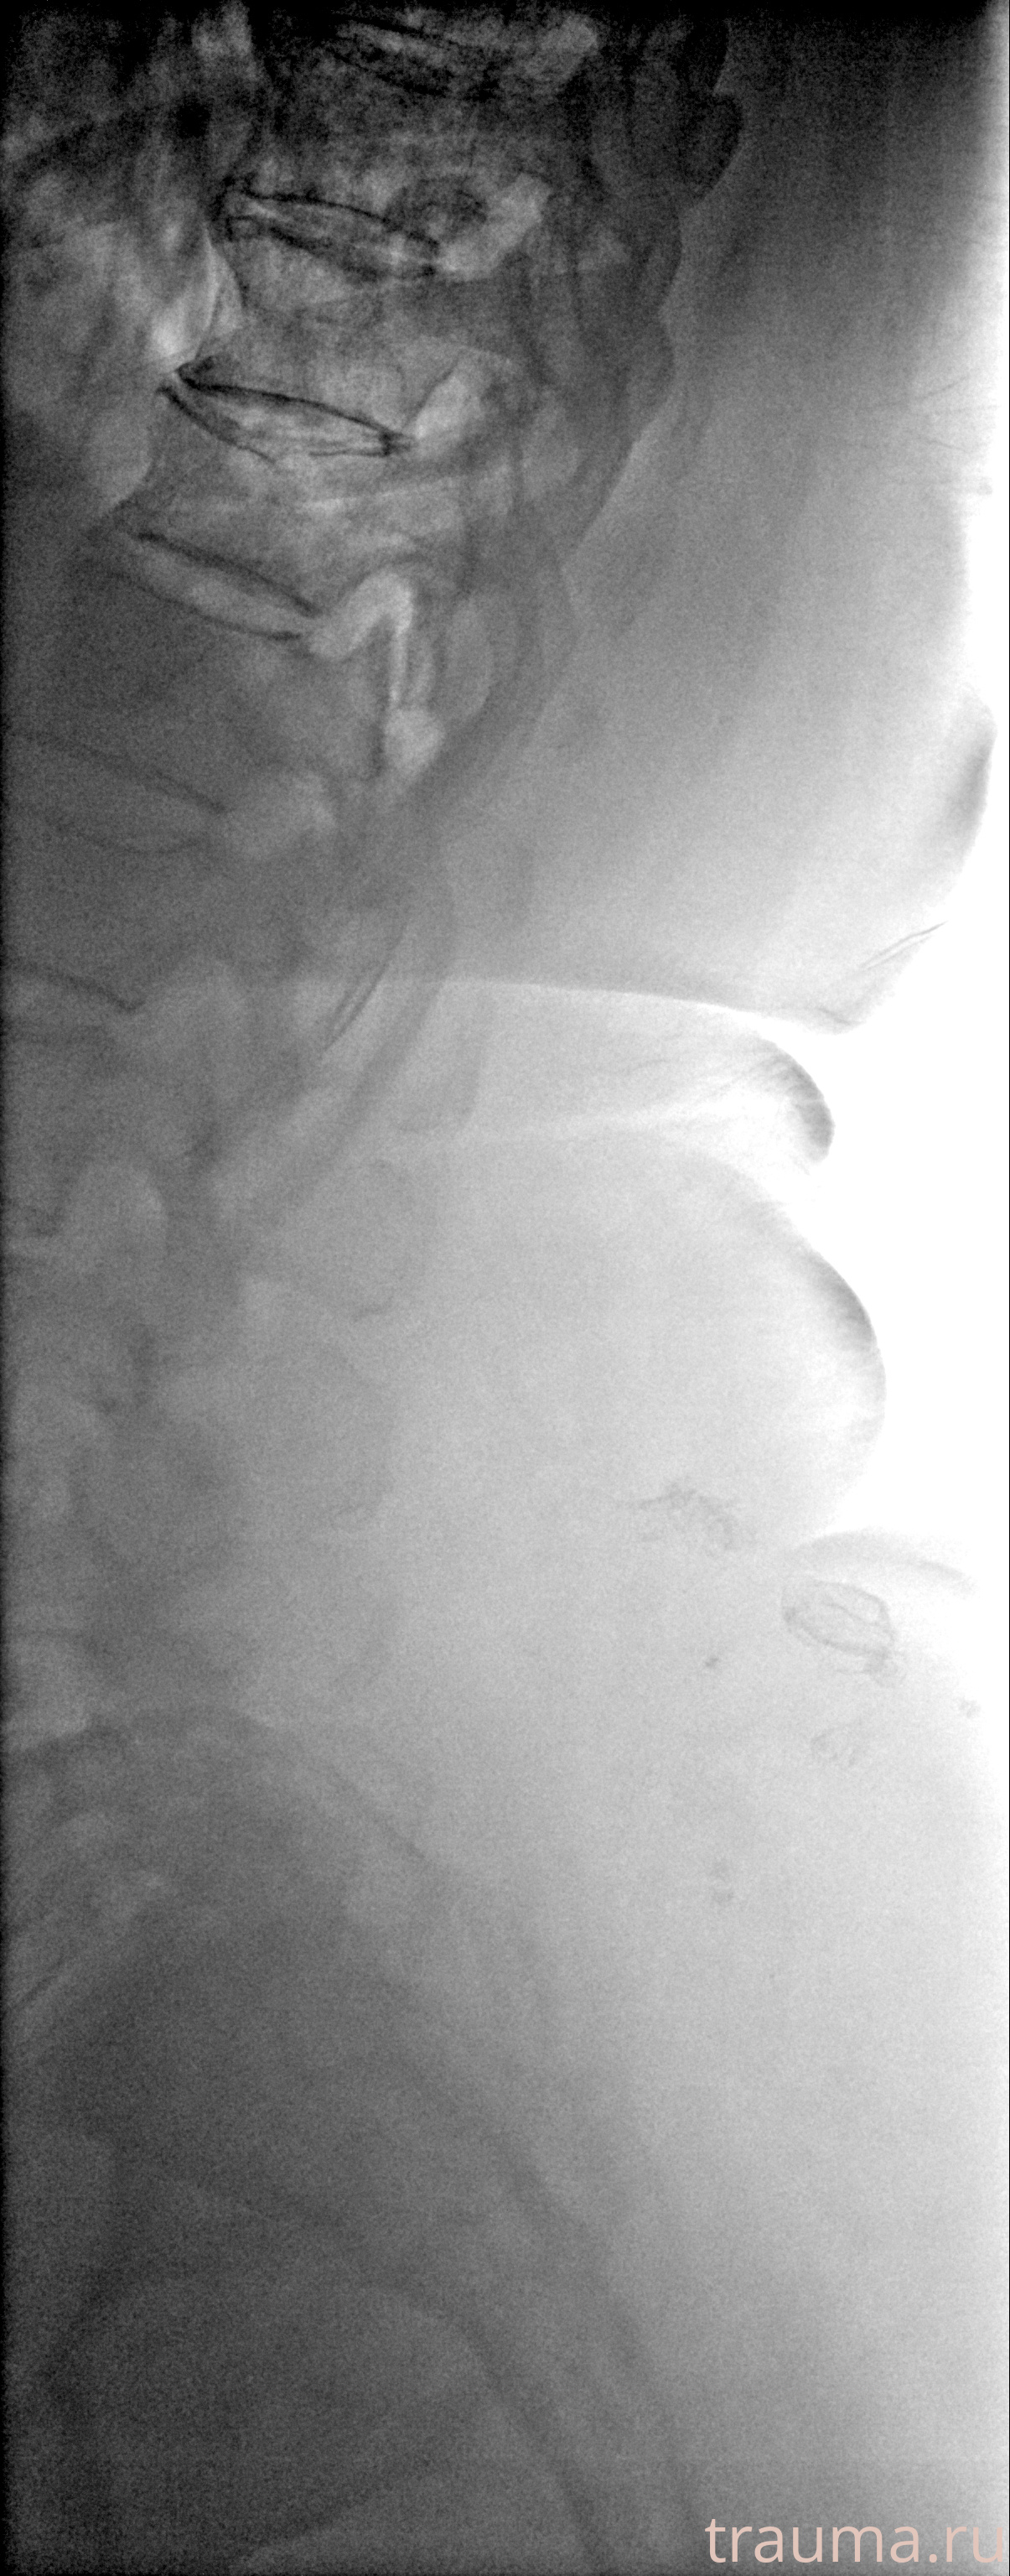

Рентген на дому: по вашему адресу приезжает врач-рентгенолог, травматолог-ортопед с мобильным рентгеновским аппаратом, проводит диагностику травмы или заболевания, делает необходимые рентгенограммы, дает рекомендации по дальнейшему лечению. Получить качественные снимки в домашних условиях возможно благодаря уникальной методике, разработанной МосРентген Центром для института  Склифосовского